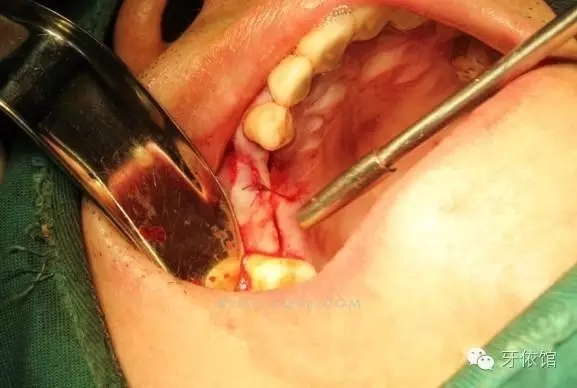

切開翻瓣

右上4,6牙位定位,先鋒鉆鉆至距離上頜竇底1-2mm處,改用CAS鉆穿透一個(gè)窩洞竇底。